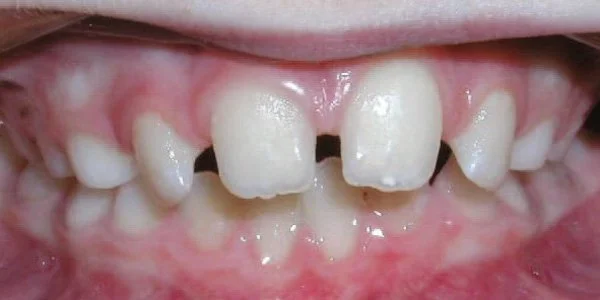

Openbite

Front teeth do not meet when teeth are closed.